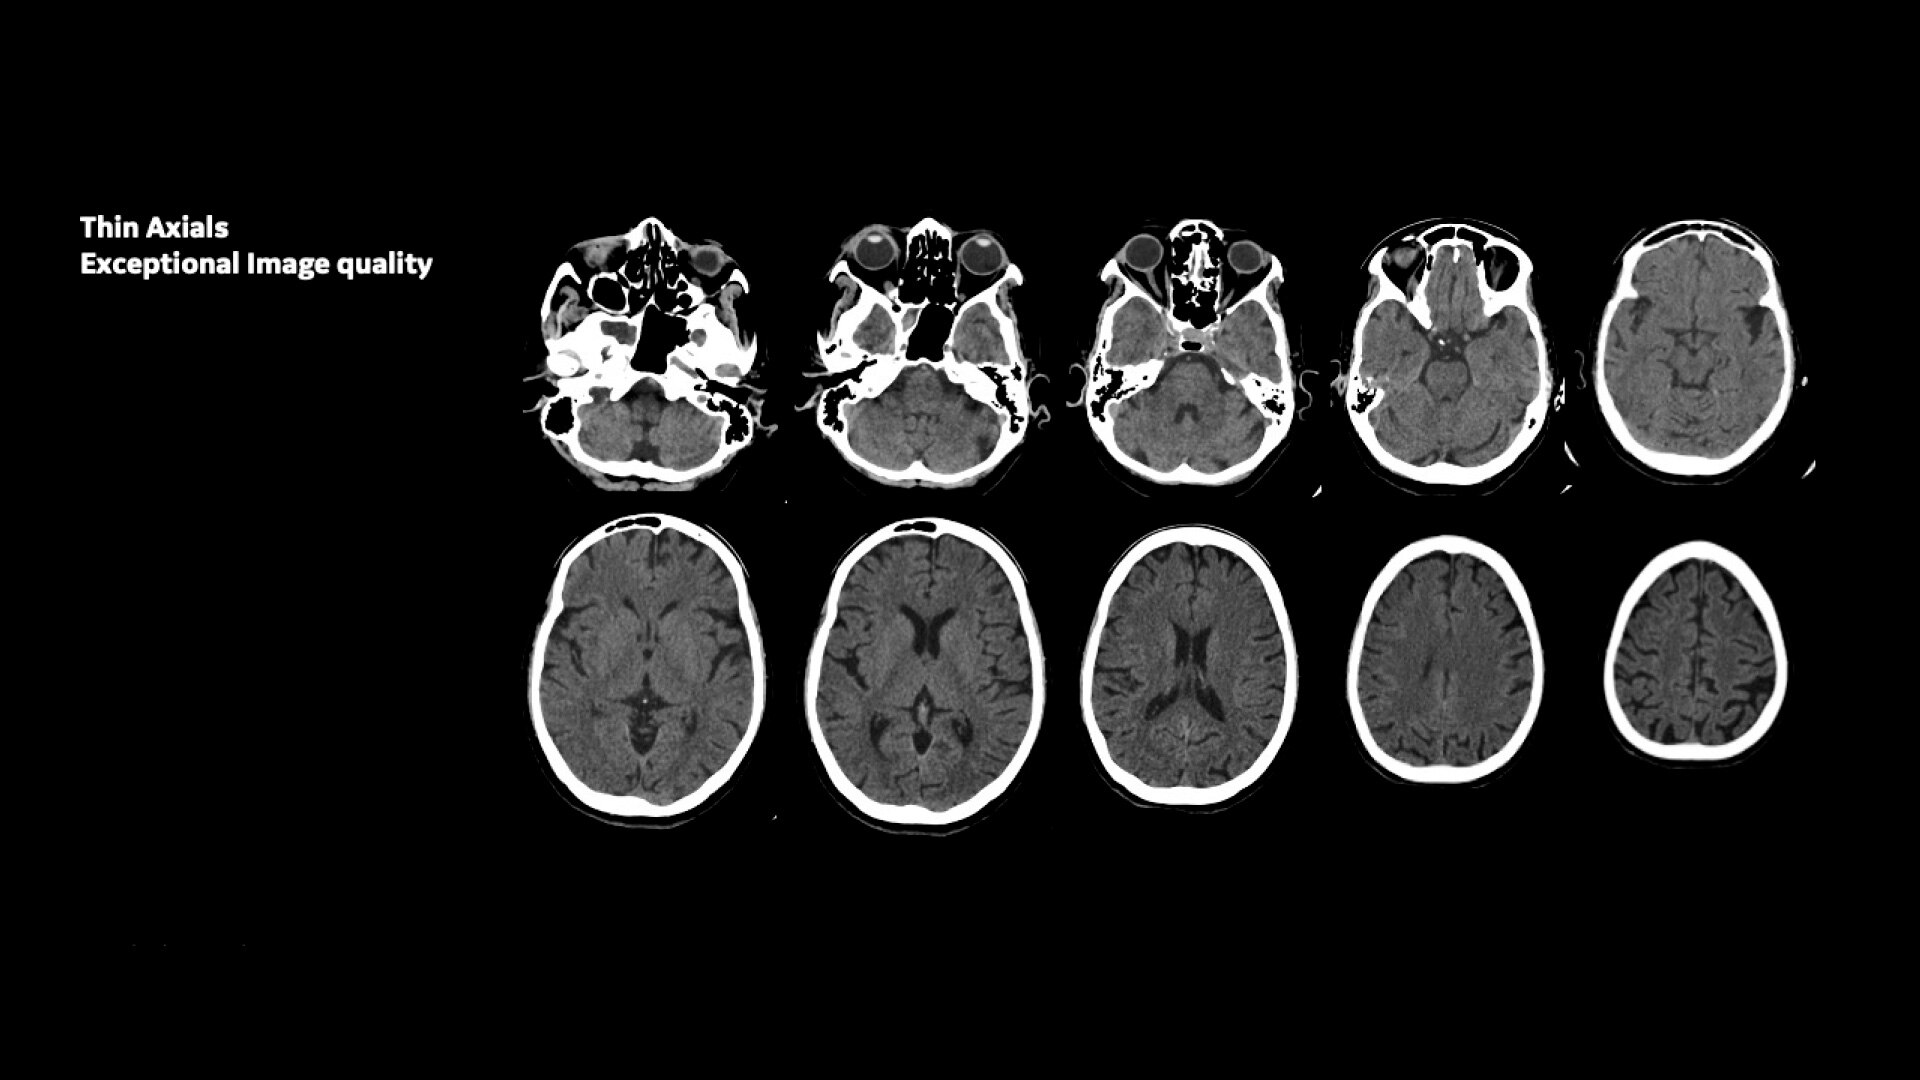

Une imagerie exceptionnelle dans un scanner IRM 1.5T à large tunnel

Une imagerie exceptionnelle dans un IRM compact 1.5 T à large tunnel